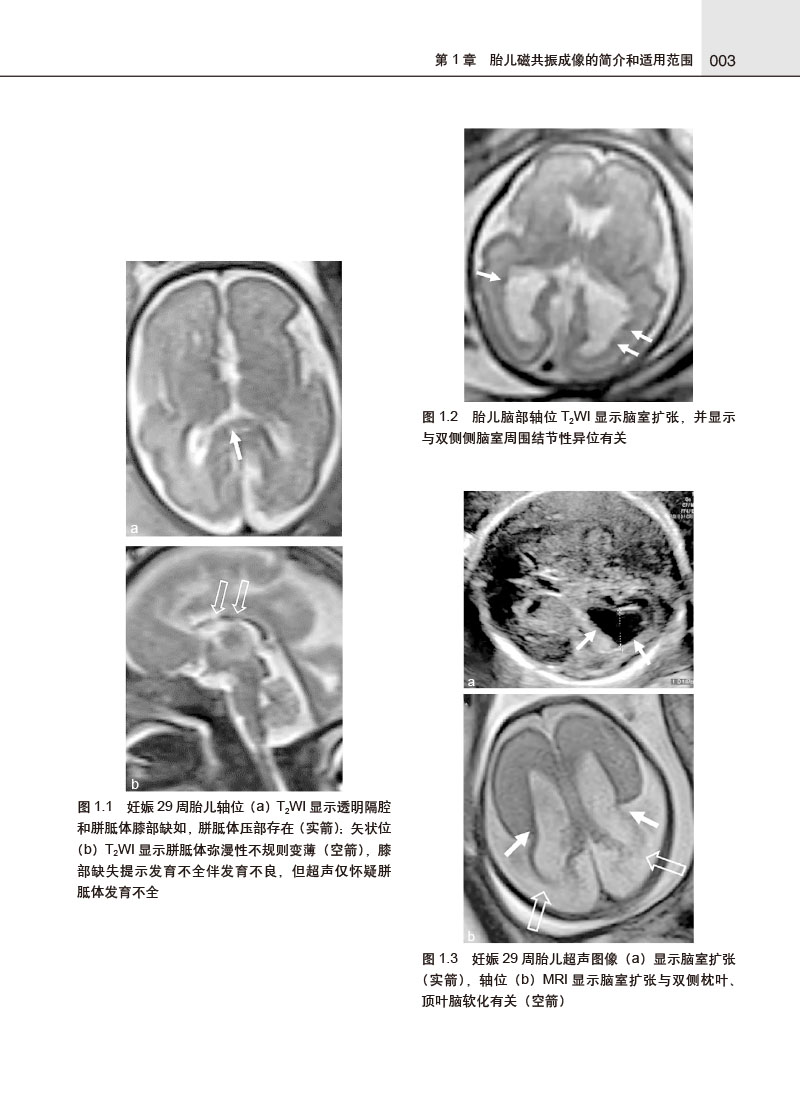

本书由国际著名胎儿磁共振成像(MRI)专家R.拉杰斯瓦拉主编,旨在全面介绍胎儿MRI临床应用的相关情况。全书对胎儿MRI检查安全性、适应证、禁忌证、检查技术、胎儿各系统MRI正常解剖及异常发育进行了全面细致的总结,并以简洁明了的方式介绍了胎儿各系统发育的基础知识,对胎儿在发育中各种异常征象配以大量插图,包括异常发育示意图、典型MRI图像,且在必要的位置增加了超声图像及产后照片做对比,强调了MRI相对于超声的优势,并提供了精准的注释。